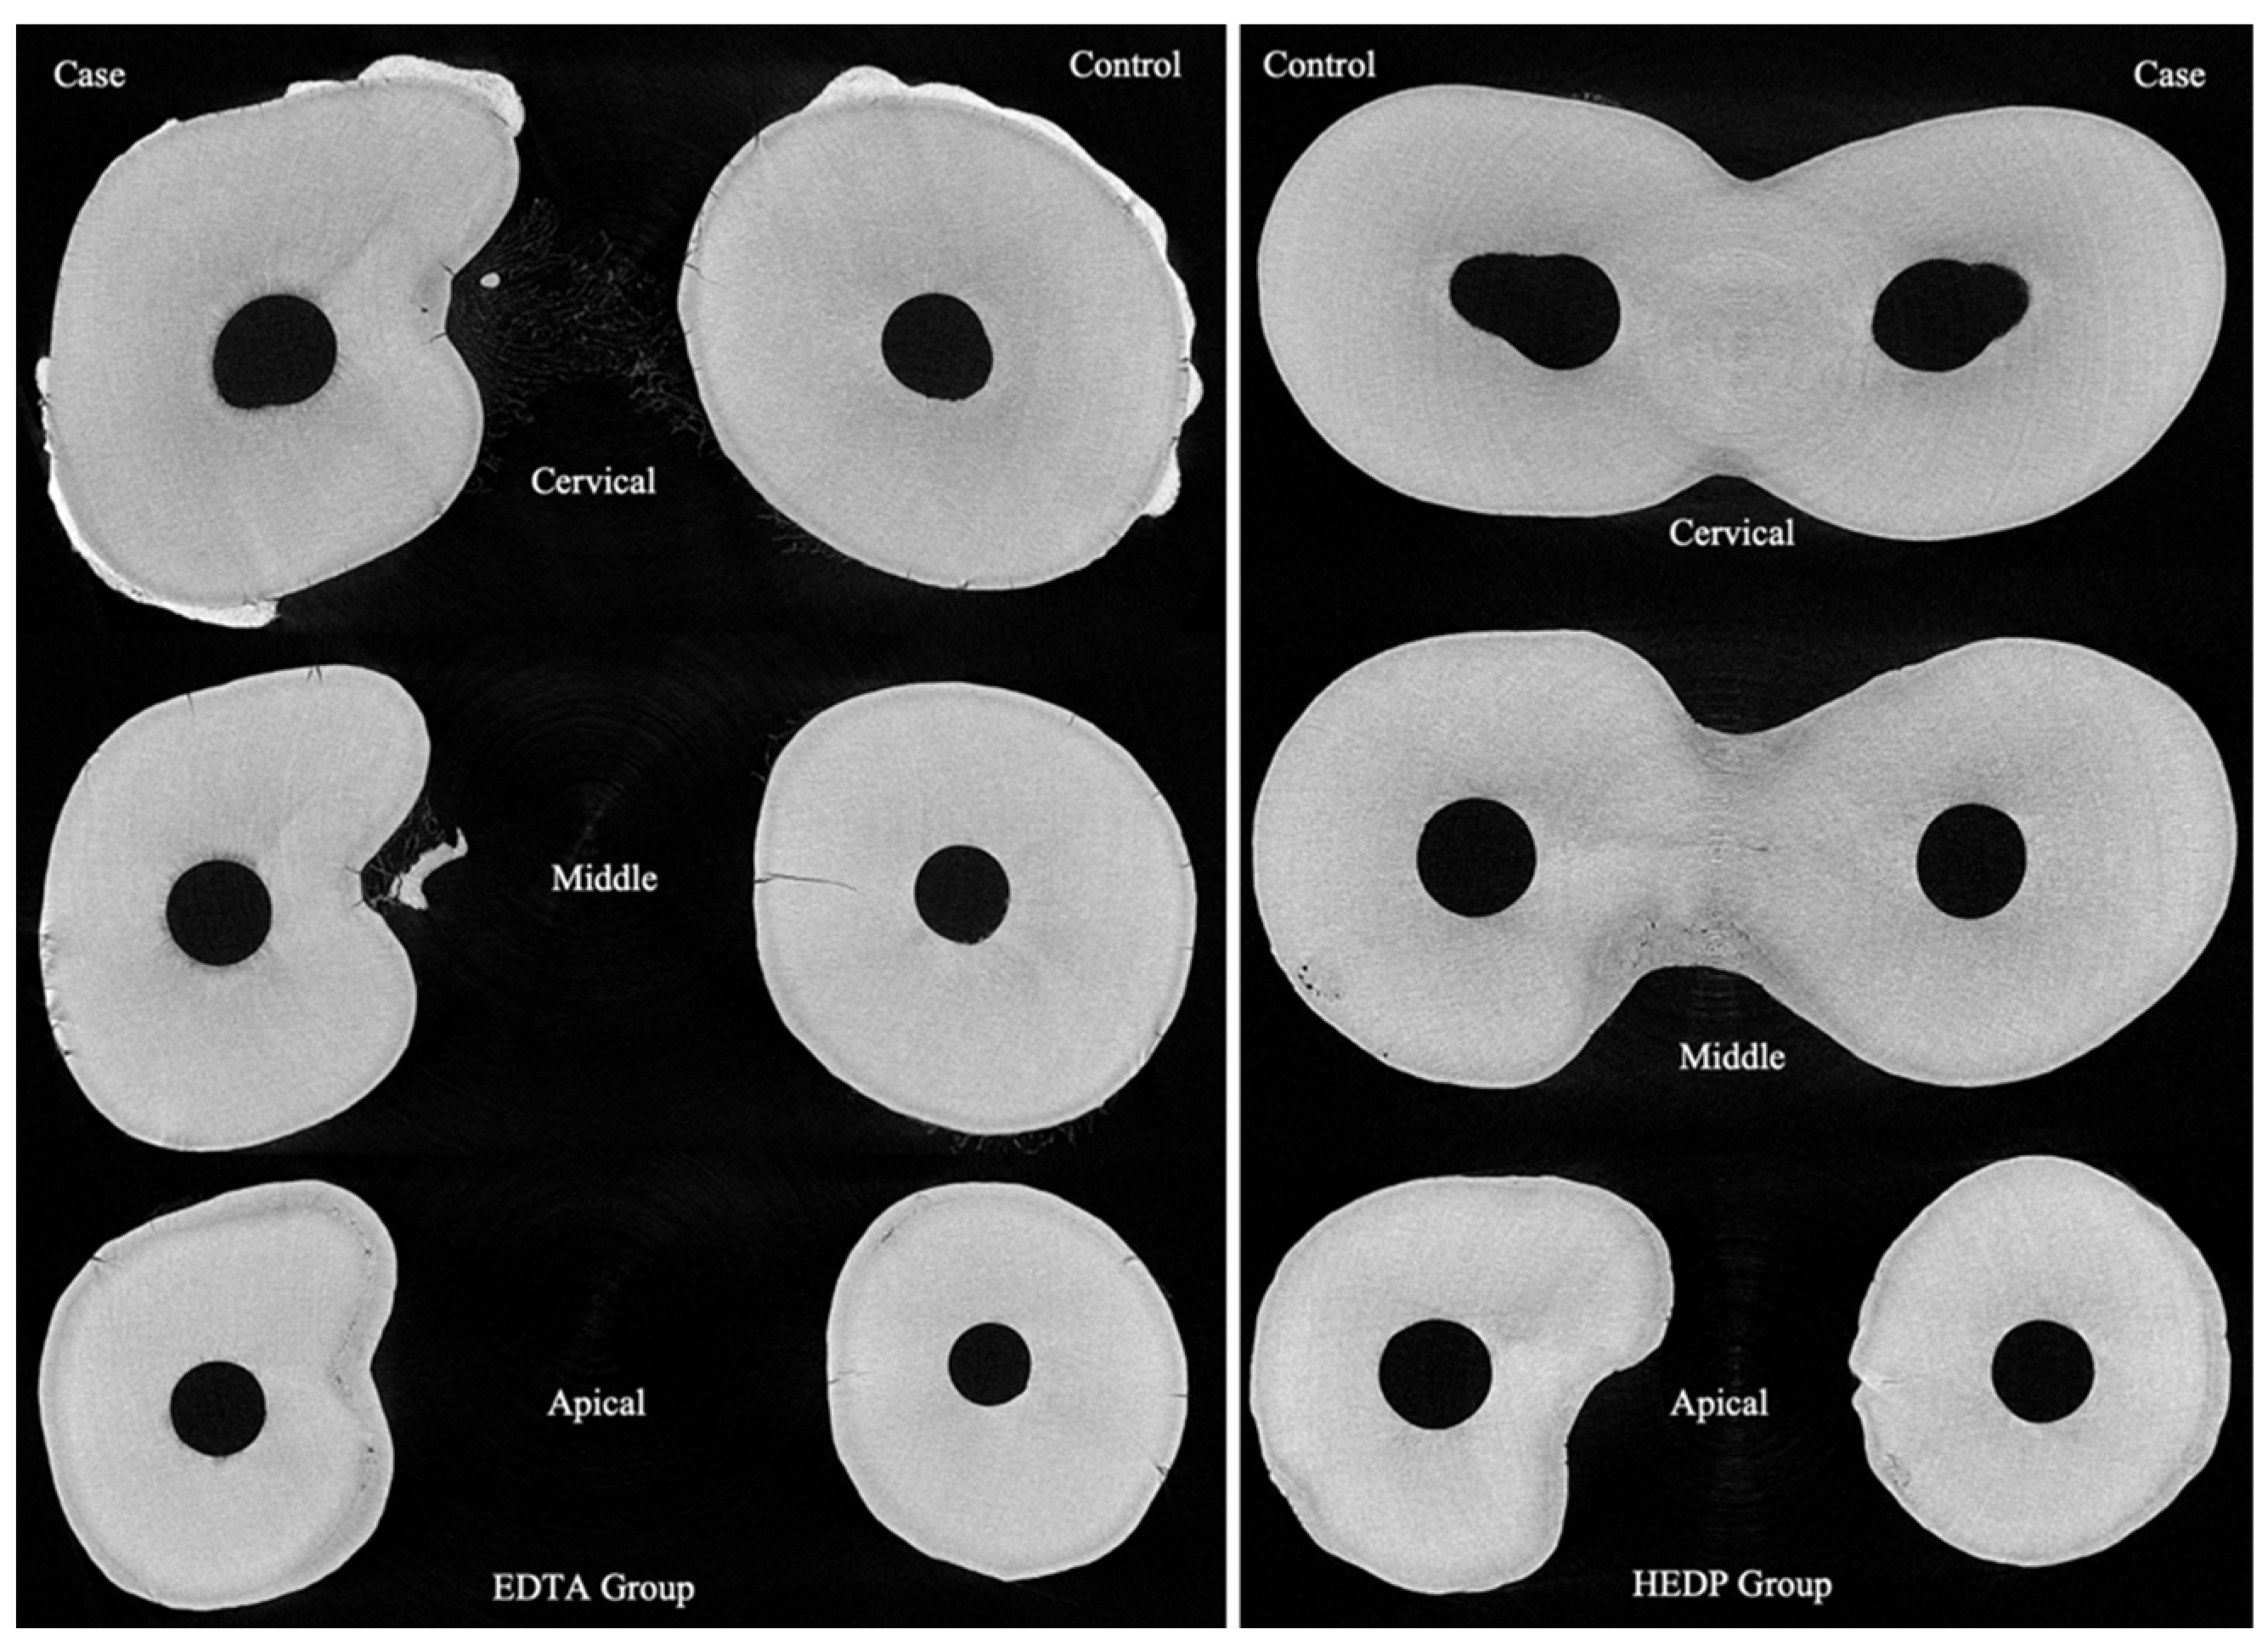

3.1. 2D Measurements

3.1.1. Descriptive